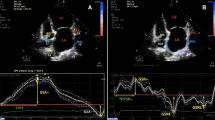

LA speckle tracking was examined in two apical projections; apical-4-chamber and apical 2-chamber. Point and click technique was used to manually trace the endocardial border of the LA. The region of interest was adjusted to fit the thickness of the atrial myocardium. In each projection, the LA was automatically divided into six segments giving longitudinal strain curves from a total of 12 segments. The QRS-complex was chosen as the baseline reference point. From the curves, LA reservoir strain (εs) corresponding to peak atrial longitudinal strain and LA contraction strain (εa) corresponding to the strain at the beginning of the P-wave during was obtained (Fig. 2). LA conduit strain (εe) was calculated as the difference between reservoir and contraction strain.